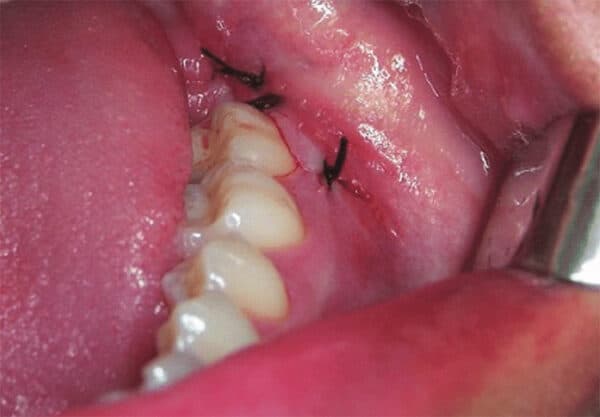

Thông thường các trường hợp nhổ răng khôn đều cần khâu lại

Vì răng khôn là chiếc răng có kích thước lớn nhất trong hàm răng, việc nhổ nó ra cần thực hiện một vết cắt lớn và sâu. Sau khi nhổ, bác sĩ cần phải khâu vết cắt này lại để giúp nó có thể lành.

1.2. Loại chỉ sử dụng để khâu

Để khâu vết cắt, bác sĩ có thể sử dụng hai loại chỉ: chỉ tự tiêu và chỉ thường. Chỉ tự tiêu có khả năng tự hấp thu trong một khoảng thời gian đủ dài để vết nhổ lành. Còn đối với chỉ thường, bệnh nhân cần quay lại nha khoa để loại bỏ chỉ theo chỉ định của bác sĩ.